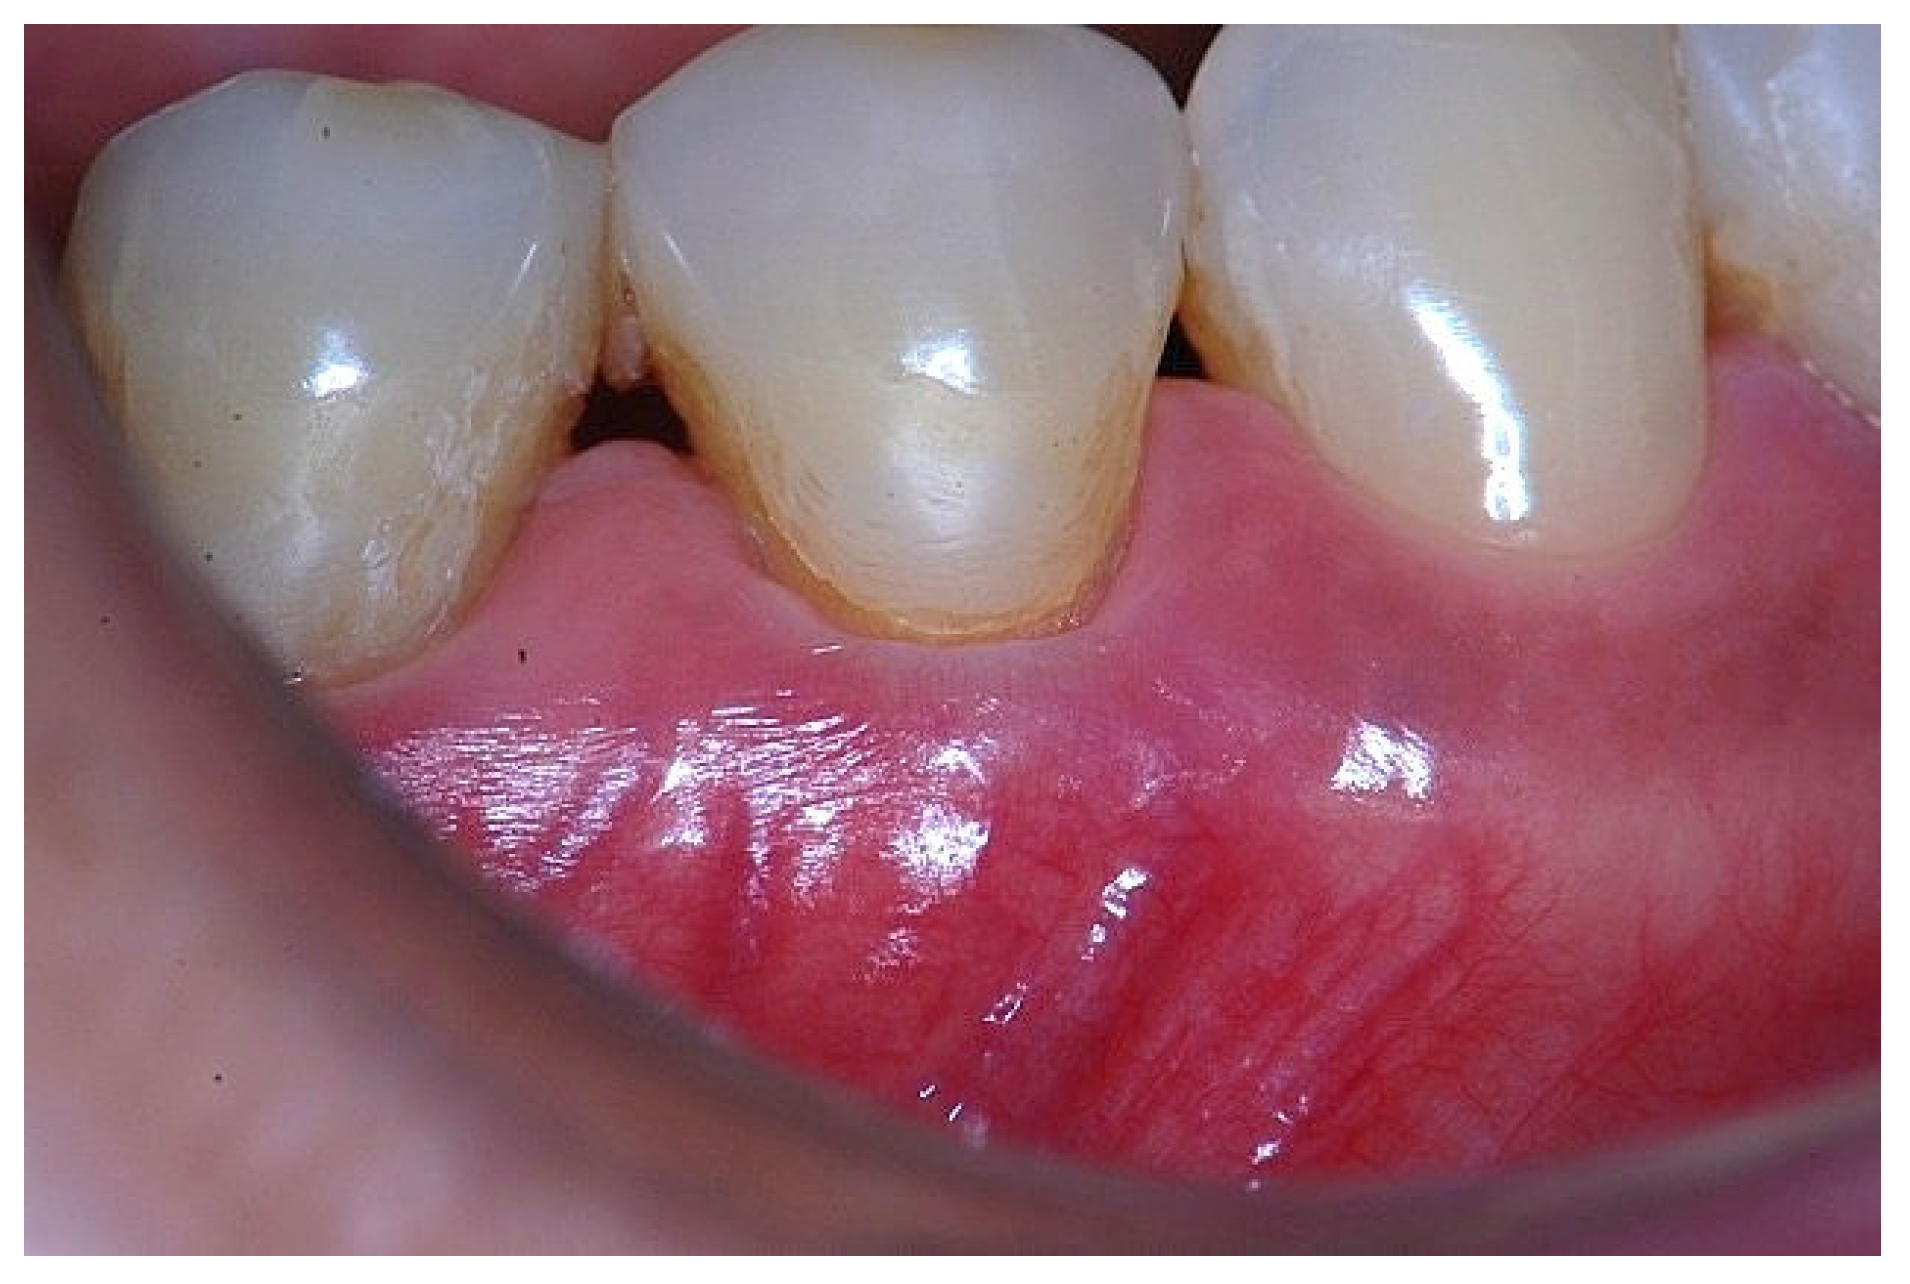

Figure 5. Apical displacement of the gingival margin observed during deep lip retraction.

In a clinical scenario with 2 mm of keratinized tissue (KT) and a sulcus depth of 1 mm, a stable, firm, and resistant connective attachment is not present [1]. This occurs because most of the connective tissue fibers inserting onto the root surface are associated with non-keratinized, mobile mucosal tissues (Figure 1), which are elastic in nature and therefore unable to stabilize the gingival margin (Figure 4 and Figure 5). Conversely, when these fibers are embedded within keratinized tissue, they are firmly attached to the tooth and bone and are comparatively immobile, thereby contributing to gingival margin stability (Figure 2, Figure 3, and Figure 6).